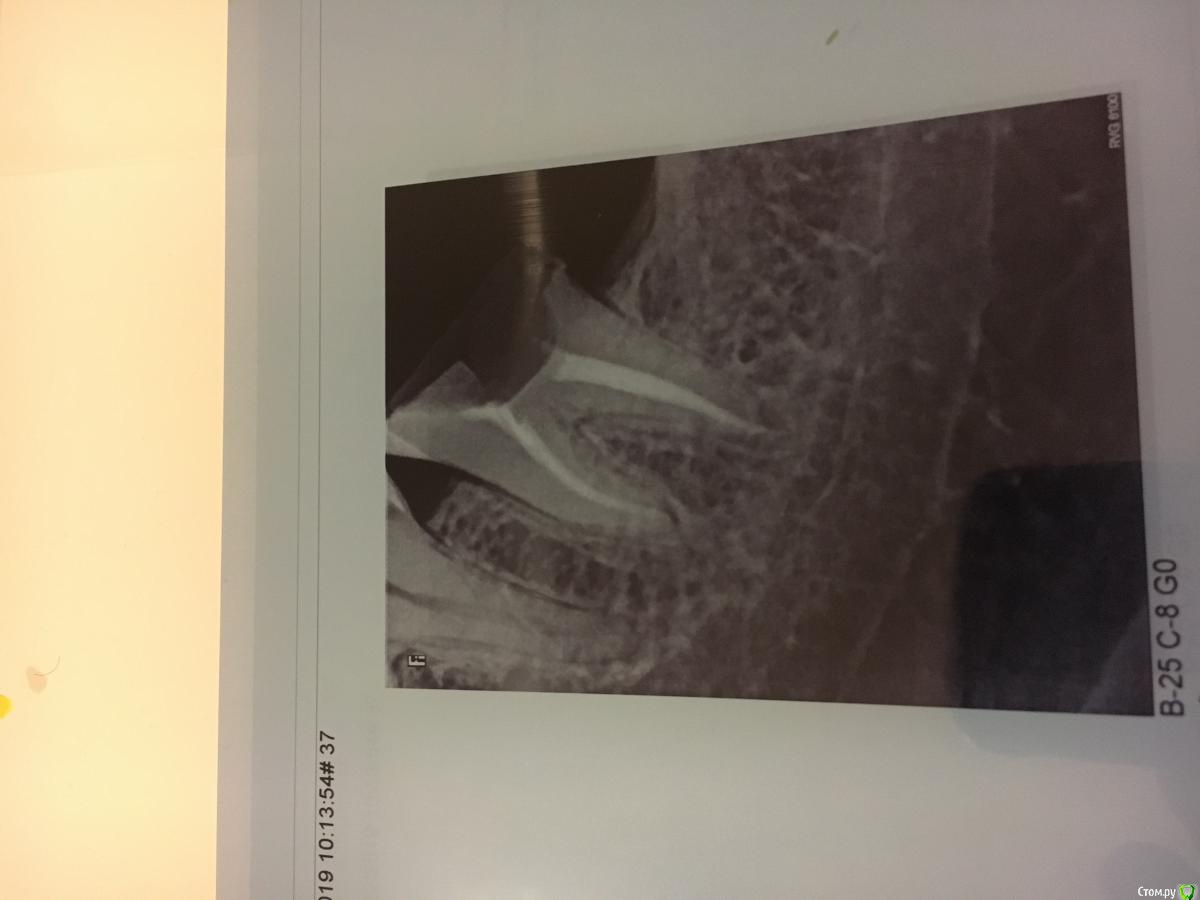

red_butler Опубликовано 1 февраля, 2019 Поделиться Опубликовано 1 февраля, 2019 http://forum.stom.ru/topic/20613-sovety-patcientam-obiazatelno-k-prochteniiu/Покажите нам снимок 2 Ссылка на комментарий

Роббоб Опубликовано 1 февраля, 2019 Автор Поделиться Опубликовано 1 февраля, 2019 Спасибо. Только разобрался как тут это делать Ссылка на комментарий

red_butler Опубликовано 1 февраля, 2019 Поделиться Опубликовано 1 февраля, 2019 Не вижу необходимости в повторном лечении Ссылка на комментарий

Doc Опубликовано 1 февраля, 2019 Поделиться Опубликовано 1 февраля, 2019 Если честно сейчас уже не вспомнюСудя по снимку он сделан недавно. А каналы лечили перед ним, год назад, много лет назад? Ссылка на комментарий

Роббоб Опубликовано 1 февраля, 2019 Автор Поделиться Опубликовано 1 февраля, 2019 Этот снимок сделан уже после похода к ортопеду. Вот снимок до. Был сделан неделю назад Ссылка на комментарий

Doc Опубликовано 1 февраля, 2019 Поделиться Опубликовано 1 февраля, 2019 Ну, если все под пломбой было, не временной, а постоянной, то можно и не лечить. Если был длительный контакт гуттаперчи в каналах со слюной, то лучше переделать. Ссылка на комментарий

Роббоб Опубликовано 1 февраля, 2019 Автор Поделиться Опубликовано 1 февраля, 2019 Зуб откололся сбоку и чуть сзади. Я так проходил месяца два. Но пломба как была на месте так и осталась. На последнем снимке вроде даже видно что со стороны десны отколото Ссылка на комментарий

DmitrySH Опубликовано 1 февраля, 2019 Поделиться Опубликовано 1 февраля, 2019 Если каналы были некоторое время разгерметизированы, то лучше сделать ревизию. Если герметично, то можно оставить. Это все можно понять при удалении пломбы Ссылка на комментарий